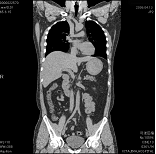

平成18年4月16日より、従来のシングル・ヘリカルCTからマルチスライス・ヘリカルCTに機種変更をしました。MDCTでは、

X線管球が身体の回りを1回転している間に極めて沢山の画像データを収集することができます。身体の中の詳細な構造を観察するためには、スライス(断面)の厚さを

薄くする必要がありますが、そうすると逆に息止めなどの検査時間が膨大なものとなってしまい、従来は不可能な方法となっていました。しかしMDCTになったことに

より、なんと10秒程度の息止め1回で例えば肺などの全域を撮影できるようになりました。

検査を受ける患者様に対するメリットとしては、

(1)今まで以上に詳細な画像を提供できる

(2)今まで以上に検査時間が短縮される

ということになります。

その結果、単に画像が速く綺麗に撮れるということにとどまらず、従来はできなかった縦方向の画像(実際に撮影しているのではなく、検査後にコンピュータで計算させて

上下方向の画像を作成するもの:MPR画像という)や、立体的な3次元画像なども従来よりもはるかに有用なものとして活用できるようになっております。

また、高知県内では限られた病院施設にしか導入されていない最新鋭の高機能CTです。当院ではこのCTを使用することにより、患者様に対してより正確でより迅速な検査を

提供することを目指しています。